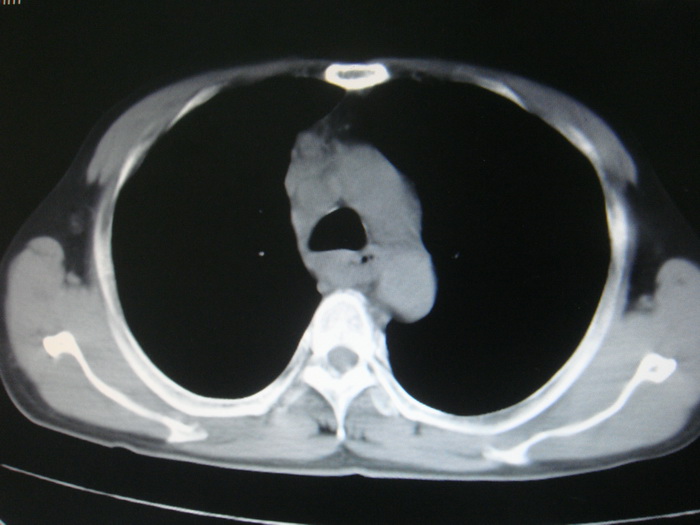

标题: CT28366:男性,45岁,偶尔发现右颈部肿块行胸部CT扫描。 [打印本页]

男性,45岁,偶尔发现右颈部肿块行胸部ct扫描。

两肺多发结节灶及纵膈淋巴结肿大考虑为转移

两肺多发性转移瘤,纵隔淋巴结转移。

两肺多发性转移瘤,纵隔淋巴结转移。食道中上段管壁似乎增厚,作相关检查。

两肺多发性转移瘤,前上纵隔淋巴结转移。